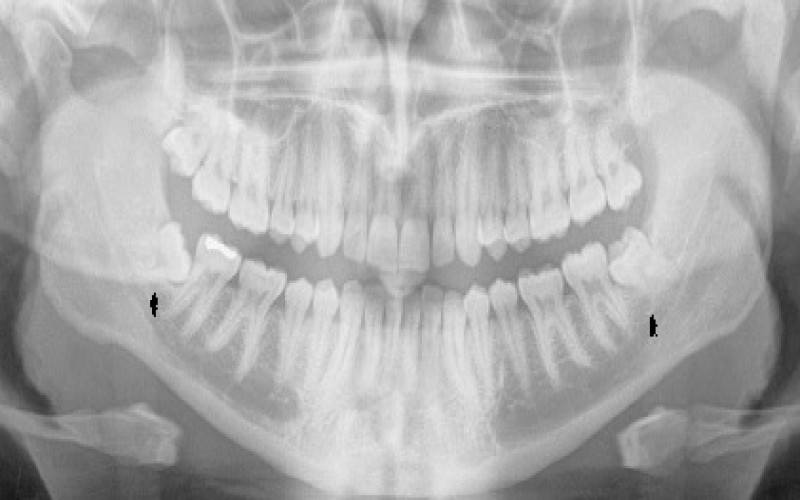

س: آیا باید قبل از جراحی عکس رادیولوژی بگیرم؟

ج: بله، عکس رادیولوژی به تشخیص دقیق موقعیت دندان و تصمیم‌گیری درباره نوع جراحی کمک می‌کند.